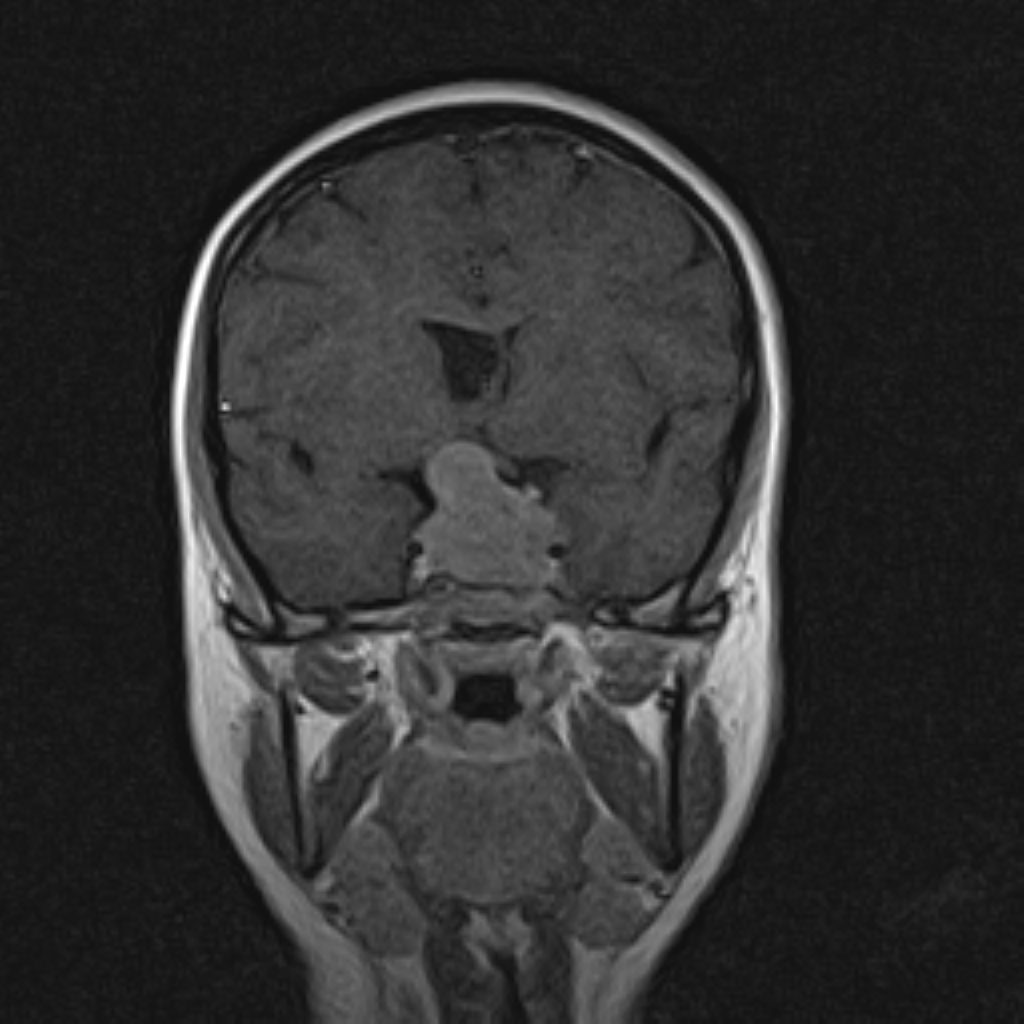

ام آر آی آتروفی عضلانی کتف بیمار

ام ار آی کتف یک روش تصویربرداری است که به وسیله آهنرباهای قدرتمند از قسمت کتف تصاویری ایجاد می کند. این نوع تصویربرداری از تشعشعات استفاده نمی کند. در این کیس آتروفی عضلانی کتف به همراه پارگی تاندون بالاخاری، بورسیت ساب دلتوئید و افیوژن مفصل دیده می شود.

– Complete tearing of supraspinatus tendon with grade 2 retraction and muscle atrophy

– AC joint hypertrophy with subacromial – subdeltoid bursitis

– Glenohumeral joint effusion